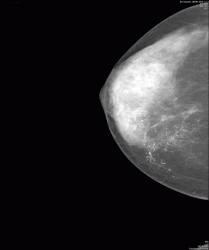

Конечно, на представленнолй маммограмме четко дифференцируется "утолщение контура" (кожи) параареолярной области. А какие еще признаки, которые свидетельствует об "раке Педжета", имеют место быть на представленном изображении?

На Ваш взгляд, практического врача, велика-ли диагностическая ценность "обнаруженных микрокальцинатов", как одного из важнейших признаков "рака молочной железы", ибо в данном случае, Вы представляете "внутрипротоковой рак" и "рак Педжета".